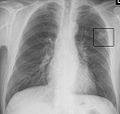

Der Unterschied zwischen der überlagerungsfreien Darstellung in der medizinischen Tomografie und einer Projektionsabbildung ist in den nachfolgenden Abbildungen illustriert. In Projektionsverfahren wie der Radiografie (gewöhnliche Röntgenuntersuchung) wird ein Schattenbild aufgenommen, auf dem sich mehrere Strukturen überlagern, wenn sie im Strahlengang hintereinander liegen. Beispielsweise überlagern beim konventionellen Röntgenbild die Weichteile der vorderen und hinteren Brustwand und die knöchernen Strukturen des Thorax die Lungenstrukturen. Dies würde die Diagnose eines Lungentumors (z. B. Bronchialkarzinom) erschweren. Jedes CT- oder MRT-Schnittbild vom Thorax zeigt dagegen nur eine 0,5 bis 10 mm dicke Schicht, die praktisch überlagerungsfrei ist.

-

Röntgenbild (Projektionsbild) eines kleinen peripheren Bronchialkarzinoms im linken Oberlappen -

Derselbe Tumor in der Computertomografie (axiales Schnittbild) -

Aus den CT-Einzelschichten zusammengesetztes 3D-Bild